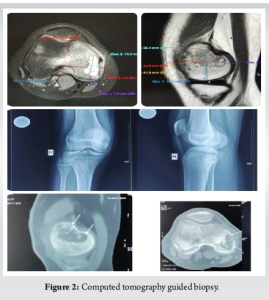

Performing a CT-guided biopsy of the right medial femoral condyle verified the chondroblastoma diagnosis (Fig. 2).